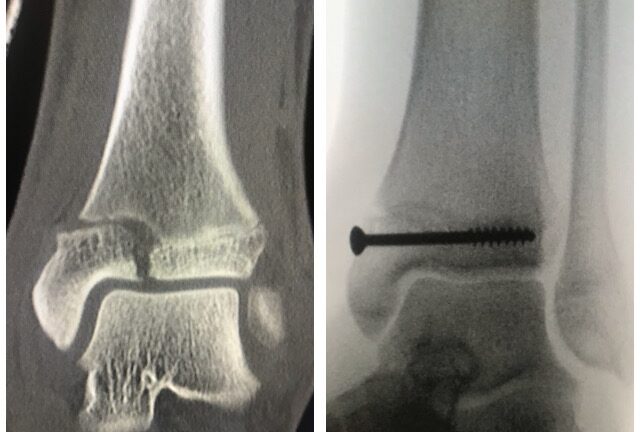

Nilkkamurtuma

Murtumakuvia

Ennen – jälkeen

Pilon murtuma

Potilas sai putoamistapaturman seurauksena hankalahoitoisen pirstaleisen sääriluun alaosan murtuman jota kutsutan Pilon mutumaksi. Pilon murtumassa sääriluun alaosan nivelpinta muistuttaa lähinnä rakkakivikkoa jonka takia se on…